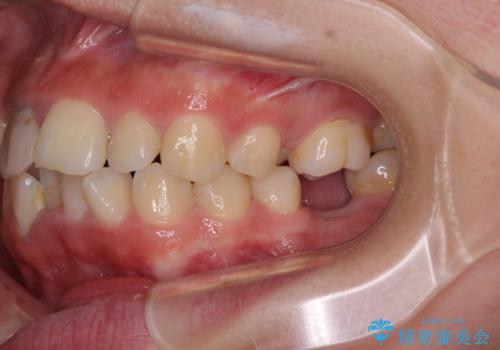

- 放置した虫歯や抜いたままの奥歯、前歯のデコボコを気にして来院された患者様です。

口元の突出感は少なく、下顎の叢生は軽微なものであったので、叢生の強い上顎左右の小臼歯を1本ずつ抜歯し、ワイヤー装置にて矯正治療を行うこととしました。

矯正治療を行う前に、根管治療の必要な上顎前歯と下顎大臼歯の根管治療を行い、矯正治療の途中で下顎の欠損部にインプラント埋入することとし、矯正治療後に補綴治療を行うこととしました。